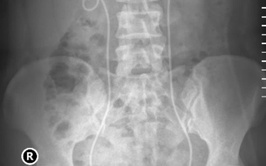

Với sự phát triển mạnh mẽ của y học hiện đại, các kỹ thuật điều trị sỏi tiết niệu đã có bước tiến vượt bậc, mang lại nhiều lựa chọn điều trị an toàn, ít xâm lấn và hiệu quả cao cho người bệnh. Tại Bệnh viện Thận Hà Nội, trung tâm chuyên khoa đầu ngành về thận - tiết niệu của Thủ đô, việc triển khai thường quy các kỹ thuật tán sỏi tiên tiến đang mở ra cơ hội điều trị tối ưu cho hàng ngàn bệnh nhân mắc bệnh lý sỏi tiết niệu.